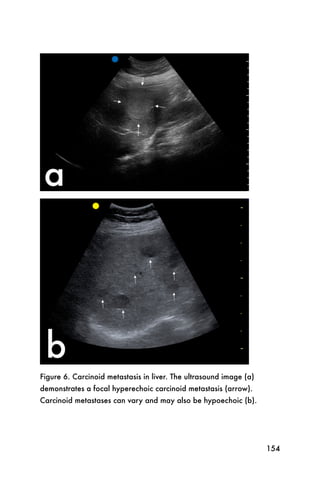

Conclusion

Ultrasound can provide valuable information about the

kidneys and help explain a patient s symptoms. Using